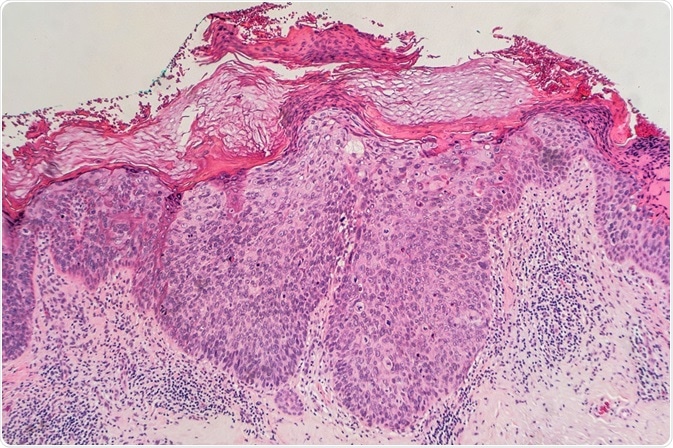

Credit: David Litman/ Shutterstock.com

Due to intradermal carcinoma,  persistent and non-elevated patched red scaly plaques occur, with a possibly cancerous outcome. These proliferate to atypical squamous cells, which resemble fish scales.